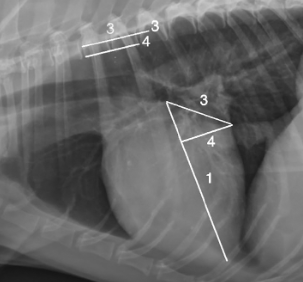

이외에도 심장의 크기를 숫자로 평가하려고 하는 수많은 노력들이 있는데

이런것도 있고